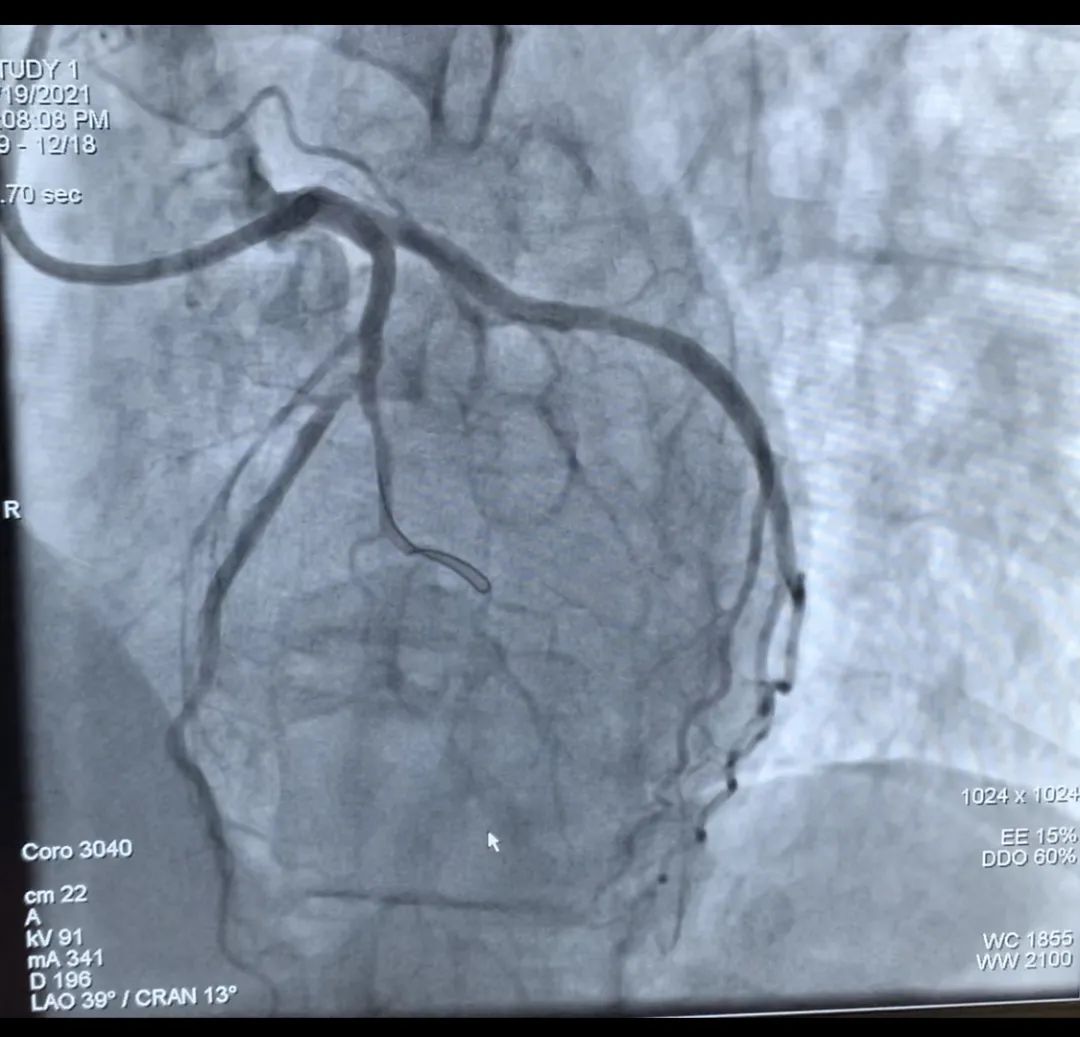

△支架植入手术中的影像图